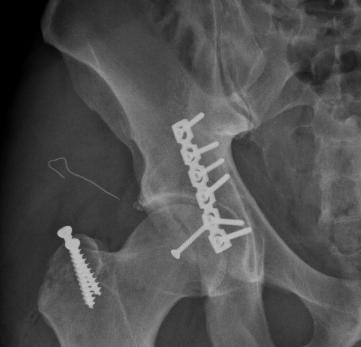

Bị tai nạn giao thông, chân phải của anh Dustin không thể cử động được và rất đau. Vào cấp cứu tại Bệnh viện Đa khoa Quốc tế Vinmec Times City lúc 3h30 sáng 29/12/2016, anh Dustin được chẩn đoán trật khớp háng hoàn toàn và vỡ cột sau ổ cối bên phải.

Chấn thương của anh Dustin khá hiếm gặp, vùng tổn thương ở sâu, vi trường phẫu thuật hạn chế, xung quanh các mảnh vỡ là dây thần kinh và mạch máu quan trọng. Với ca chấn thương này, TS Nghĩa và các bác sĩ Vinmec đã tiến hành nắn trật khớp trở lại, đồng thời kết xương bằng nẹp vít ổ cối thành công cho người bệnh trong ca mổ kéo dài hơn 4h. Ba ngày sau mổ, Dustin đã bắt đầu tập đi. Và 6 ngày sau, anh đã được ra viện, đồng thời định kỳ đến tập phục hồi chức năng theo các bài tập chuyên sâu tại bệnh viện.